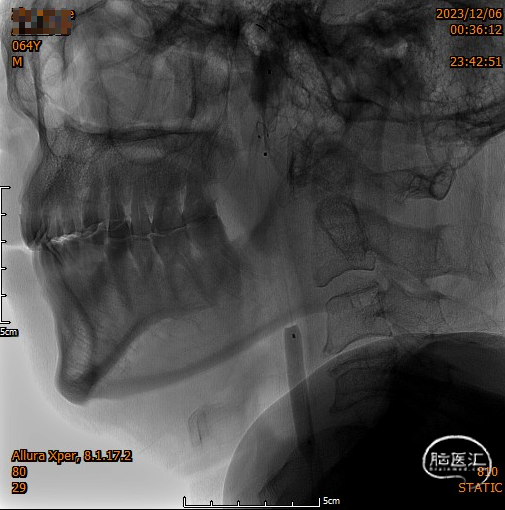

头颈部CTA

DSA